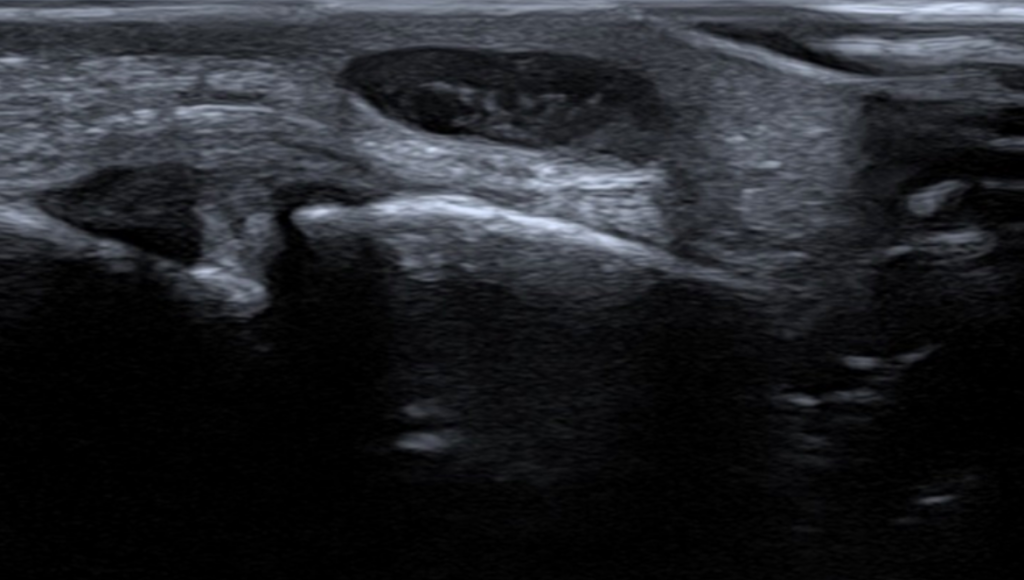

En pasient ble henvist til plastikkirurg i desember på grunn av en klump på den proksimale og dorsale del av venstre 3. finger. Røntgen var normalt. Ultralyd ble utført på […]